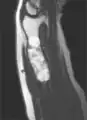

X-ray showing enchondromas localized in the humerus of a 37-year-old patient affected with Ollier disease

MRI showing enchondromas localized in the lower part of the radius of a 37-year-old patient affected with Ollier disease

MRI showing enchondromas localized in the lower part of the radius of a 37-year-old patient affected with Ollier disease.

Enchondromas localized in the upper part of the humerus of the same patient